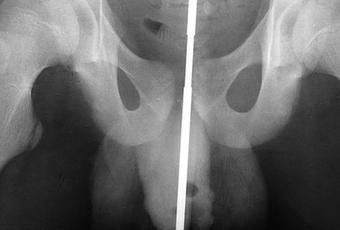

Una vez que haya viajado a la sala de emergencias después de esta inserción de cuerpo extraño, ocurrirán una serie de eventos para ayudar a los médicos a comprender lo que ha ocurrido. Se le harán preguntas, el médico tendrá que visualizar lo que ha ocurrido sin tocar el objeto para limitar el daño y tendrá que realizar estudios de imagen para tener una comprensión clara de lo que ha ocurrido.

El último procedimiento que se realiza para eliminar el objeto depende completamente de qué y dónde se puede encontrar el objeto. Es posible que deba someterse a una cirugía para extirpar algunos de los músculos y ligamentos que podrían afectar al objeto. Lo que también sería necesario probablemente sería una uretrografía retrógrada. Esta es una evaluación médica donde se insertará un tubo con una cámara en la uretra para verificar si hay daños. También puede extenderse hacia la vejiga para evaluar mejor el daño interno potencial que podría haber ocurrido.